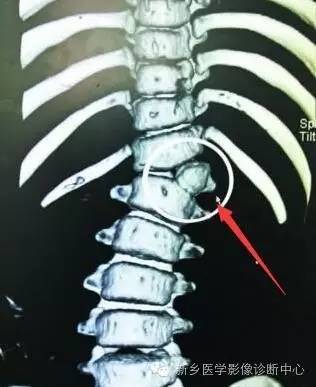

蝴蝶椎:椎体中央矢状位裂隙存在,椎体由两个尖端相对的楔形块构成,形状如蝴蝶。

脊椎椎体畸形(半椎体、蝴蝶椎)